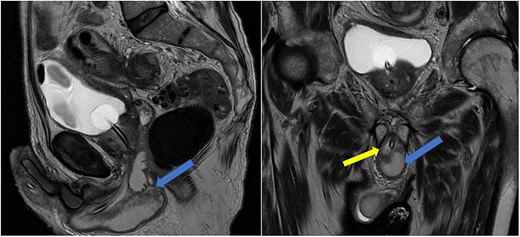

Imaging was suggestive of an infected Cowper’s syringocele. As the patient was clinically stable, a trial of antibiotic therapy was suggested. Repeat MRI a week later showed that the collection had extended into the corpus spongiosum, which now appeared expanded with the fluid density signal (Fig. 1). On a review, the urethral catheter was thought to be impairing potential drainage of the collection. It was removed, and a suprapubic catheter was inserted. Ultrasound guided aspiration failed to drain a significant amount of pus, which also grew S. anginosus. There was also radiological suspicion of a colovesical fistula. The patient was reviewed by the colorectal surgeons, who felt that as there were no other symptoms relating to the fistula, and the patient was physiologically frail, and defunctioning of the bowel would be inappropriate. Likewise, the patient was deemed too frail for any surgical management of the collection. He was discharged after a total of 6 weeks’ antibiotics. Repeat MRI 4 months later (Fig. 2) showed a smaller but persistent collection.

Case 1: T2-weighted axial image 4 months later, showing slight reduction in the size of the collection (arrow).

In view of his significant comorbidities and the absence of any clinical signs or symptoms, he is being managed conservatively with a long-term suprapubic catheter.